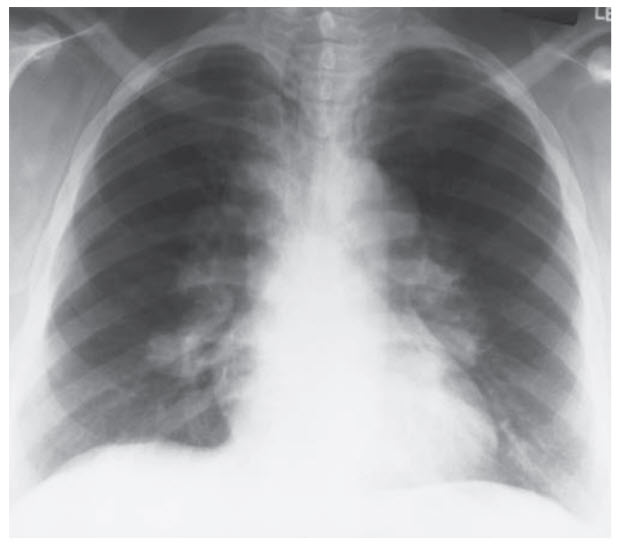

A 32-year-old African American woman presents to the hospital with chest pain, cough, and difficulty breathing. Symptom onset has been gradual over the past few months. She has not traveled recently or been exposed to any sick contacts, and she has no personal or family history of cardiac disease. She works as an elementary school teacher and does not smoke or use illicit drugs. On examination, the patient is afebrile and her vitals are normal. The patient is admitted and a chest x-ray is obtained (Figure below).

Angiotensin-converting enzyme. The risk of sarcoidosis is increased in African American patients, and is suggested by the development of chronic symptoms of chest pain, cough, and dyspnea. Sarcoidosis is a granulomatous disease that most commonly affects the lungs but can affect many other organs including the skin (granulomatous nodules, erythema nodosum), eyes (uveitis), heart (restrictive cardiomyopathy, conduction disturbances), nervous system (neurosarcoid), and more. The cause is unknown. Diagnosis can be made by putting together the clinical symptoms and risk factors, obtaining a chest x-ray that shows bilateral hilar adenopathy (Figure above), and performing a biopsy that shows noncaseating granulomas. If pulmonary function tests are performed, a restrictive pattern may be seen.